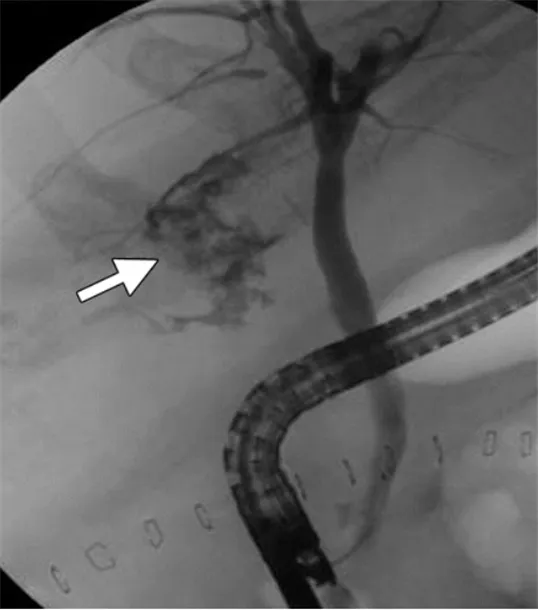

48세 여성이 만성 담낭염으로 복강경하 담낭절제술을 시행받았다. 수술 후 4일째 환자의 공막에 황달이 나타났다. 혈액검사 및 내시경역행담췌관조영술(ERCP) 결과는 아래와 같다. 이 환자에게 적절한 처치는 무엇인가?

Imp: iatrogenic biliary leak

ERCP에서 cystic duct stump clipping site로 조영제 누출이 관찰되고 있다. cholecystectomy 후 cystic duct(담낭관)의 결찰이 불완전하게 되어 누출이 있는 것으로 보인다. ERCP 시술 중 stent를 CBD에 삽입하여 수술적 처치 없이 leak를 방지할 수 있으며, 복강 내로 leakage로 인해 fluid collection이 있는 경우 경피적배액술을 시행할 수 있다.